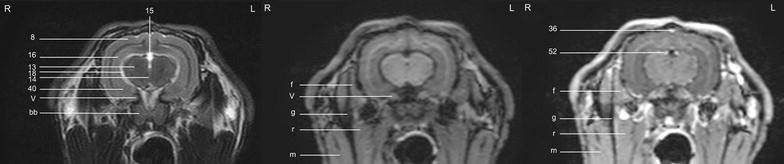

Fig. 5.

Transverse images of the rabbit brain at the level of the olfactory bulb (left T2w; middle T1w; right T1w post-contrast)

Fig. 6.

Transverse images of the rabbit brain at the level of the olfactory bulb/rostral telencephalon (left T2w; middle T1w; right T1w post-contrast)

Fig. 7.

Transverse images of the rabbit brain at the level of the rostral telencephalon/rhinal fissure (left T2w; middle T1w; right T1w post-contrast)

Fig. 8.

Transverse images of the rabbit brain at the level of the mid telencephalon (left T2w; middle T1w; right T1w post-contrast)

Fig. 9.

Transverse images of the rabbit brain at the level of the rostral part of the hypophysis (left T2w; middle T1w; right T1w post-contrast)

Fig. 10.

Transverse images of the rabbit brain at the level of the caudal part of the hypophysis (left T2w; middle T1w; right T1w post-contrast)

Fig. 11.

Transverse images of the rabbit brain at the level of the thalamus (left T2w; middle T1w; right T1w post-contrast)

Fig. 12.

Transverse images of the rabbit brain at the level of the mesencephalic aqueduct (left T2w; middle T1w; right T1w post-contrast)

Fig. 13.

Transverse images of the rabbit brain at the level of the rostral cerebellum (left T2w; middle T1w; right T1w post-contrast)